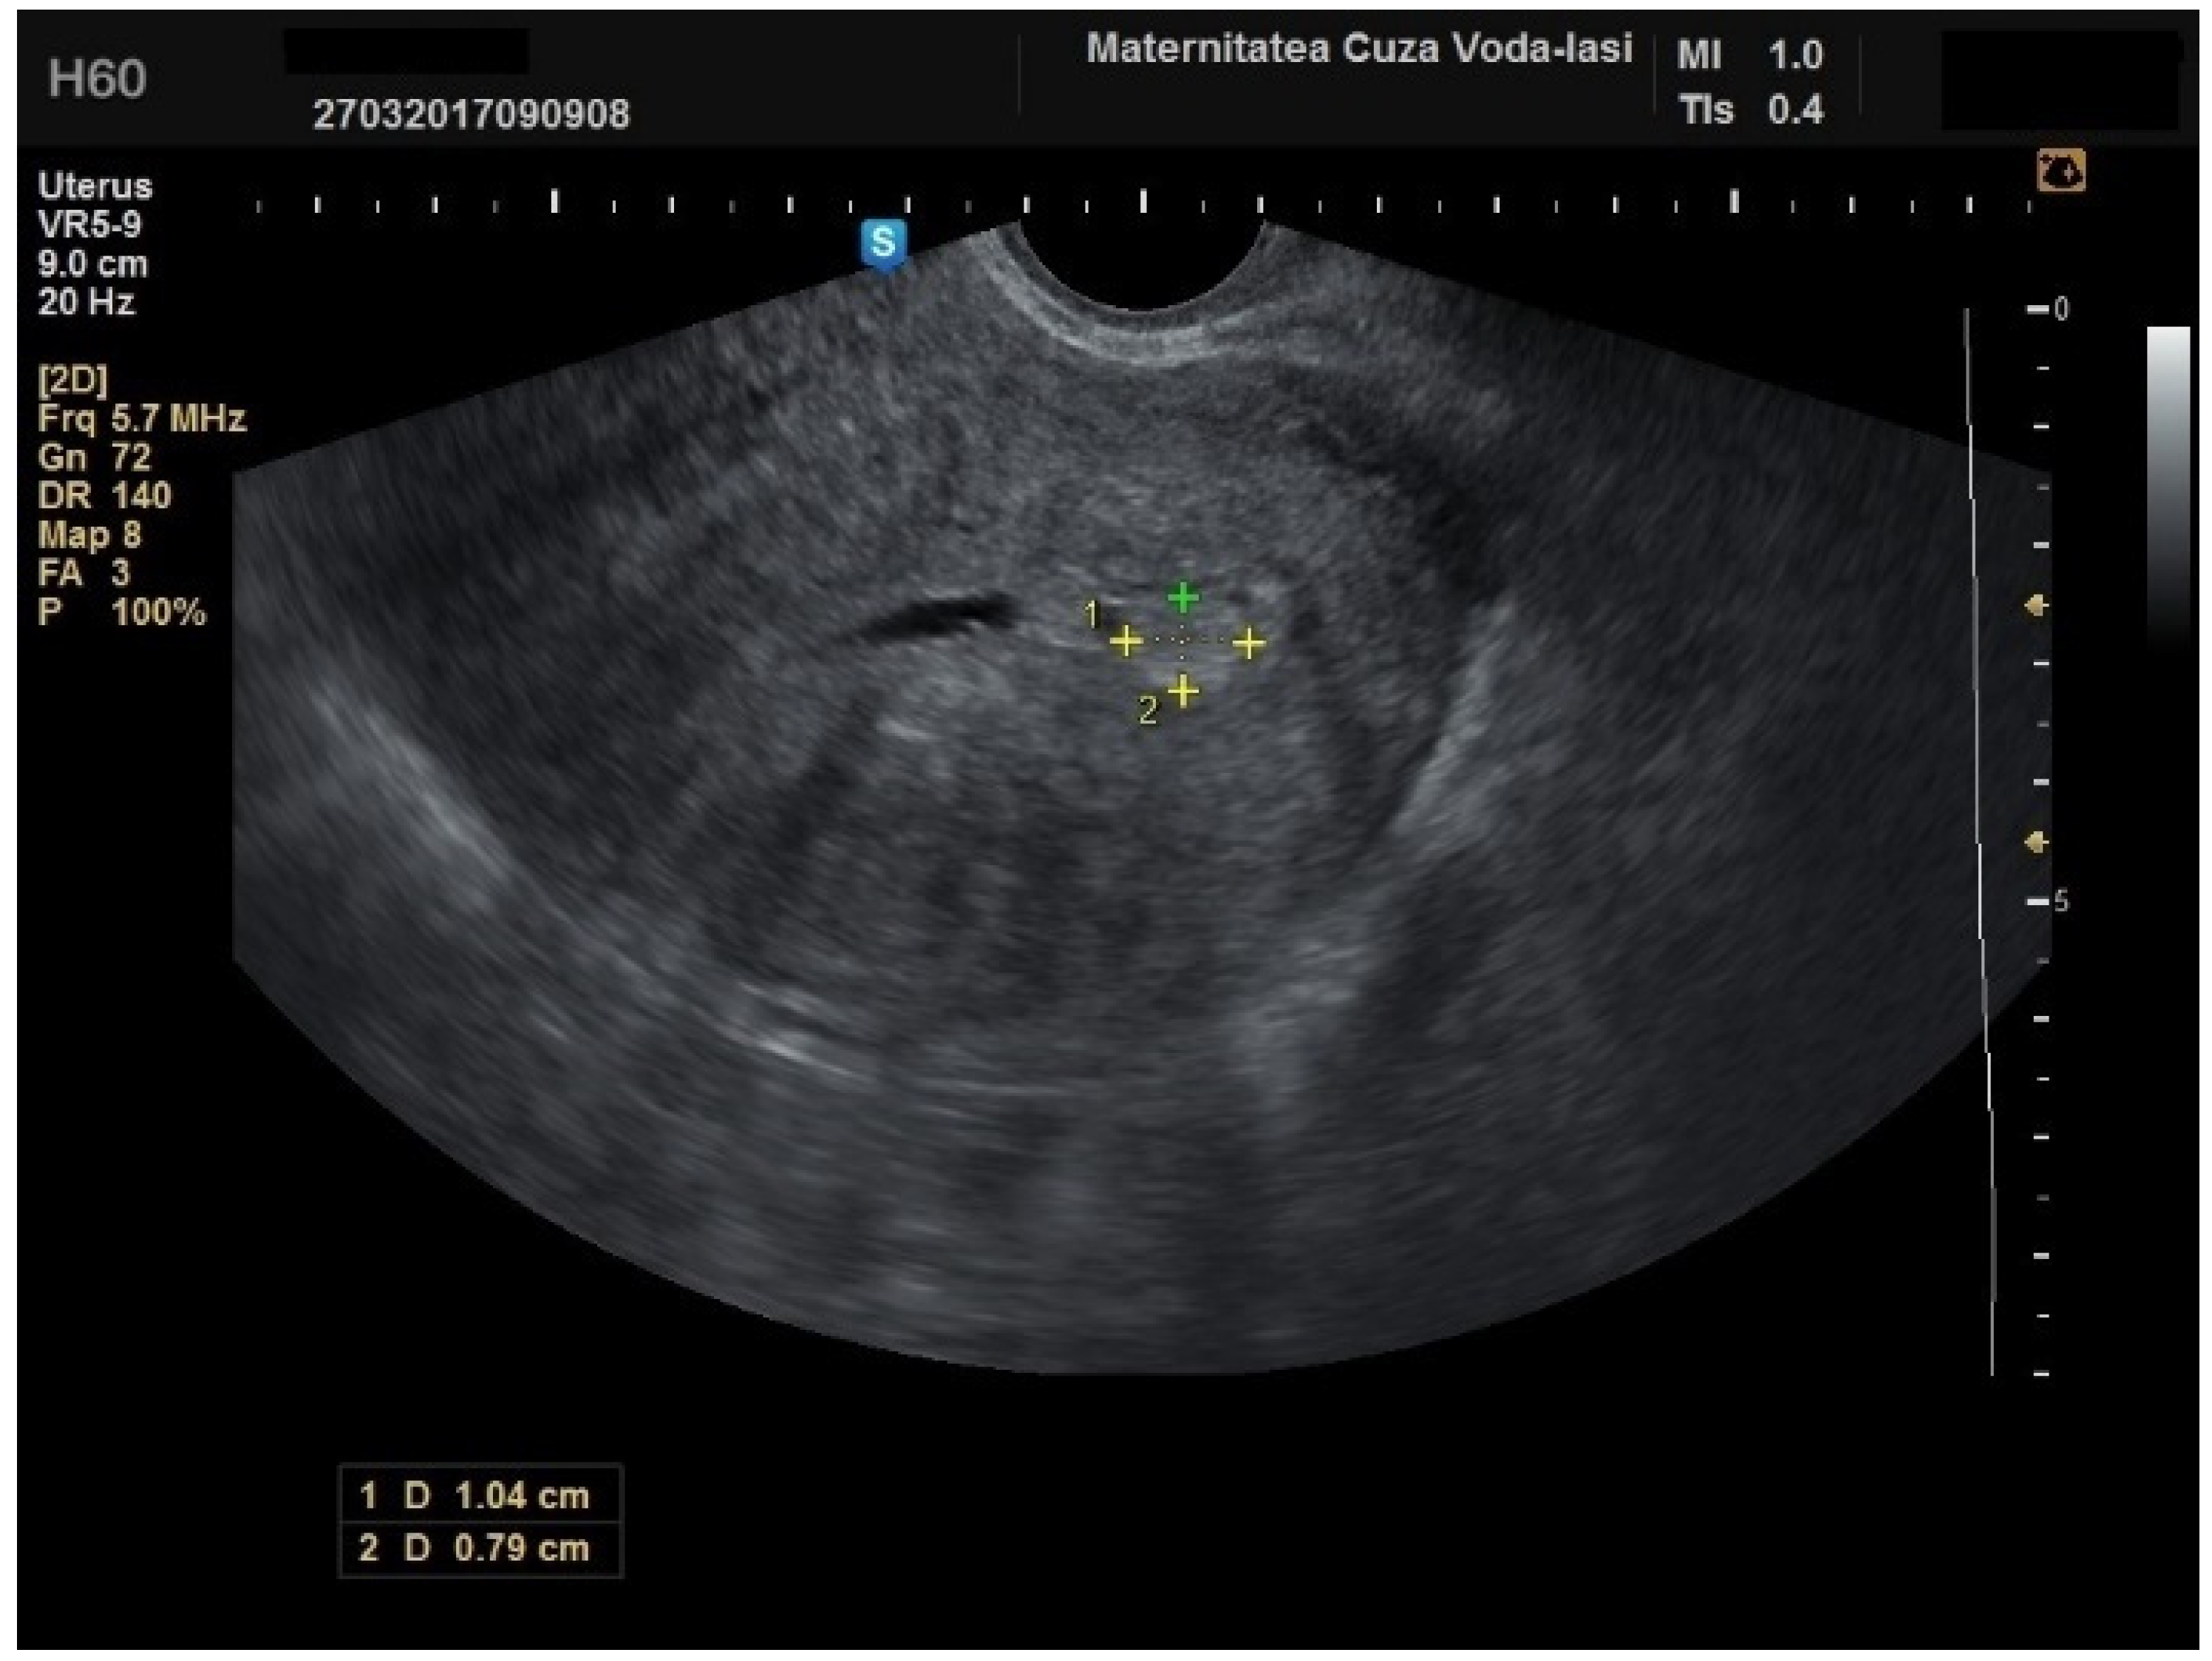

Figure 3. Ultrasonographic imaging of endometrial polyps.

The mean age for patients with endometrial polyps was 50.70 ± 8.40 years (p = 0.001). The average endometrial thickness for the endometrial polyps was 13.68 ± 4.37 mm (p = 0.001), with a threshold value of 9.8 mm, yielding a sensitivity of 0.767, and specificity of 0.23, which lacked predictive value. There was no correlation between the internal structure of the endometrium and its echogenic homogeneity—heterogenous endometrium showed a sensitivity of 90.9% (95% CI: 0.7219 to 0.9747) and specificity of 46.51% (95% CI: 0.3251 to 0.6108) (Figure 15). The endometrial–myometrial junction remained regular in all cases of endometrial polyps. Usually, the vascular score for polyps was 1, with a single dominant vessel penetrating from the myometrium into the endometrium, either with (Figure 16) or without branching (Figure 17), although vascularization was not observed in 68.4% of participants with polyps.

The average endometrial thickness, as measured by transvaginal ultrasonography, was found to be 18.02 ± 10.94 mm (range: 5–64 mm). Malignancy was identified in 22.84% of cases with uterine cavity findings. The mean endometrial thickness for women diagnosed with endometrial cancer was 24.49 ± 13.33 mm (95% confidence interval [CI]: 14.34 to 35.16), (Figure 2), whereas those with other pathologies had a mean thickness of 16.10 ± 9.37 (95% CI: 13.14 to 18.57), (Figure 3), with statistical significance (p = 0.028). When endometrial thickness was used as a standalone variable to build a model for estimating the risk for endometrial malignancy it demonstrated the highest AUC with a value of 0.682 (95% CI: 0.452–0.912). A cut-off threshold of 26 mm for endometrial thickness yielded a sensitivity of 62.5% and a specificity of 89% (Figure 4).